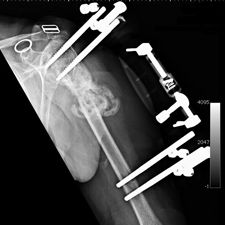

Some time in late May 2010, she presented with movement of the fracture site and was noted that the central area of healing had broken down and was thought that she had a deep infection. She was taken back to theater in mid June 2010 when operation showed that there was no pus. Multiple samples of the fracture site were taken and an external fixator applied with compression of the fragments. Following that, the cultures taken from the wounds showed no growth and no organisms and a biopsy showed no sign of any malignancy or abnormal cells. The fixator became loose and eventually had to be removed. This was done in July 2010 and she was discovered to be going onto a hypertrophic nonunion. Low dose ultrasound treatment of the fracture site was tried to help stimulate healing over the course of a few months but the non union persisted.

She was advised of the need to do some sort of stabilization which is necessary since the use of low-dose ultrasound has not helped in the healing process. She was unwilling to have any further operative intervention and sought further options. Eventually, she agreed to a fourth procedure of intra-medullary nail stabilization of the fracture and had this carried out in April 2011. An intramedullary nail was inserted in an antegrade manner and she has since gone on to heal the fracture site completely and has regained most of the function of the upper limb with no pain.